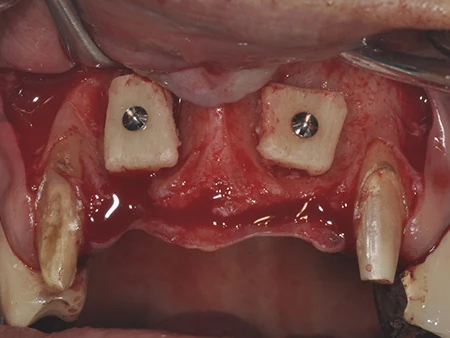

下顎の奥(親知らずが生える部分の横あたり)からブロックの塊の骨を採取し、チタンスクリューで骨に固定します。

固定した骨の周りにウシ由来の人工骨を移植します。